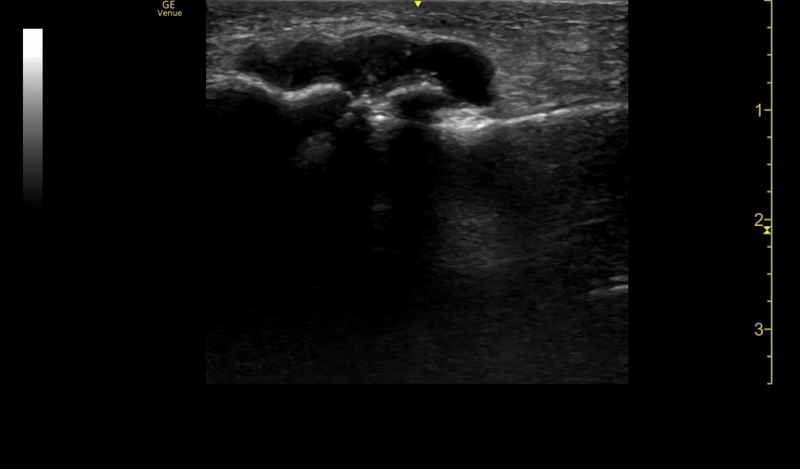

On point-of-care ultrasound (POCUS), a small joint effusion on the affected left big toe is seen with a maximum diameter of about 5mm.

An ultrasound guided arthrocentesis was performed using in-line needle visualization technique.

Ultrasound as a tool is highly effective in detecting joint fluid given its high sensitivity (Draghi et al), lack of radiation, cost effectiveness, and its use in rapid bedside assessment. To do so — use a linear probe to find the joint in the long axis and identify the hypoechoic fluid in relation to the joint space. Scan both in long and short axes to fully characterize the effusion. When performing a musculoskeletal ultrasound, you should always examine the affected joint as well as the contralateral unaffected side for comparison.

In our case, we were dealing with an effusion that measured 0.5cm by 2cm at its largest dimensions – it was a tiny effusion. Without the use of ultrasound, obtaining fluid from this tiny pocket would have been very difficult. The patient’s MTP was prepped using sterile procedure and an ultrasound probe cover was utilized to ensure sterility. We used in-line technique, as demonstrated in the above video.